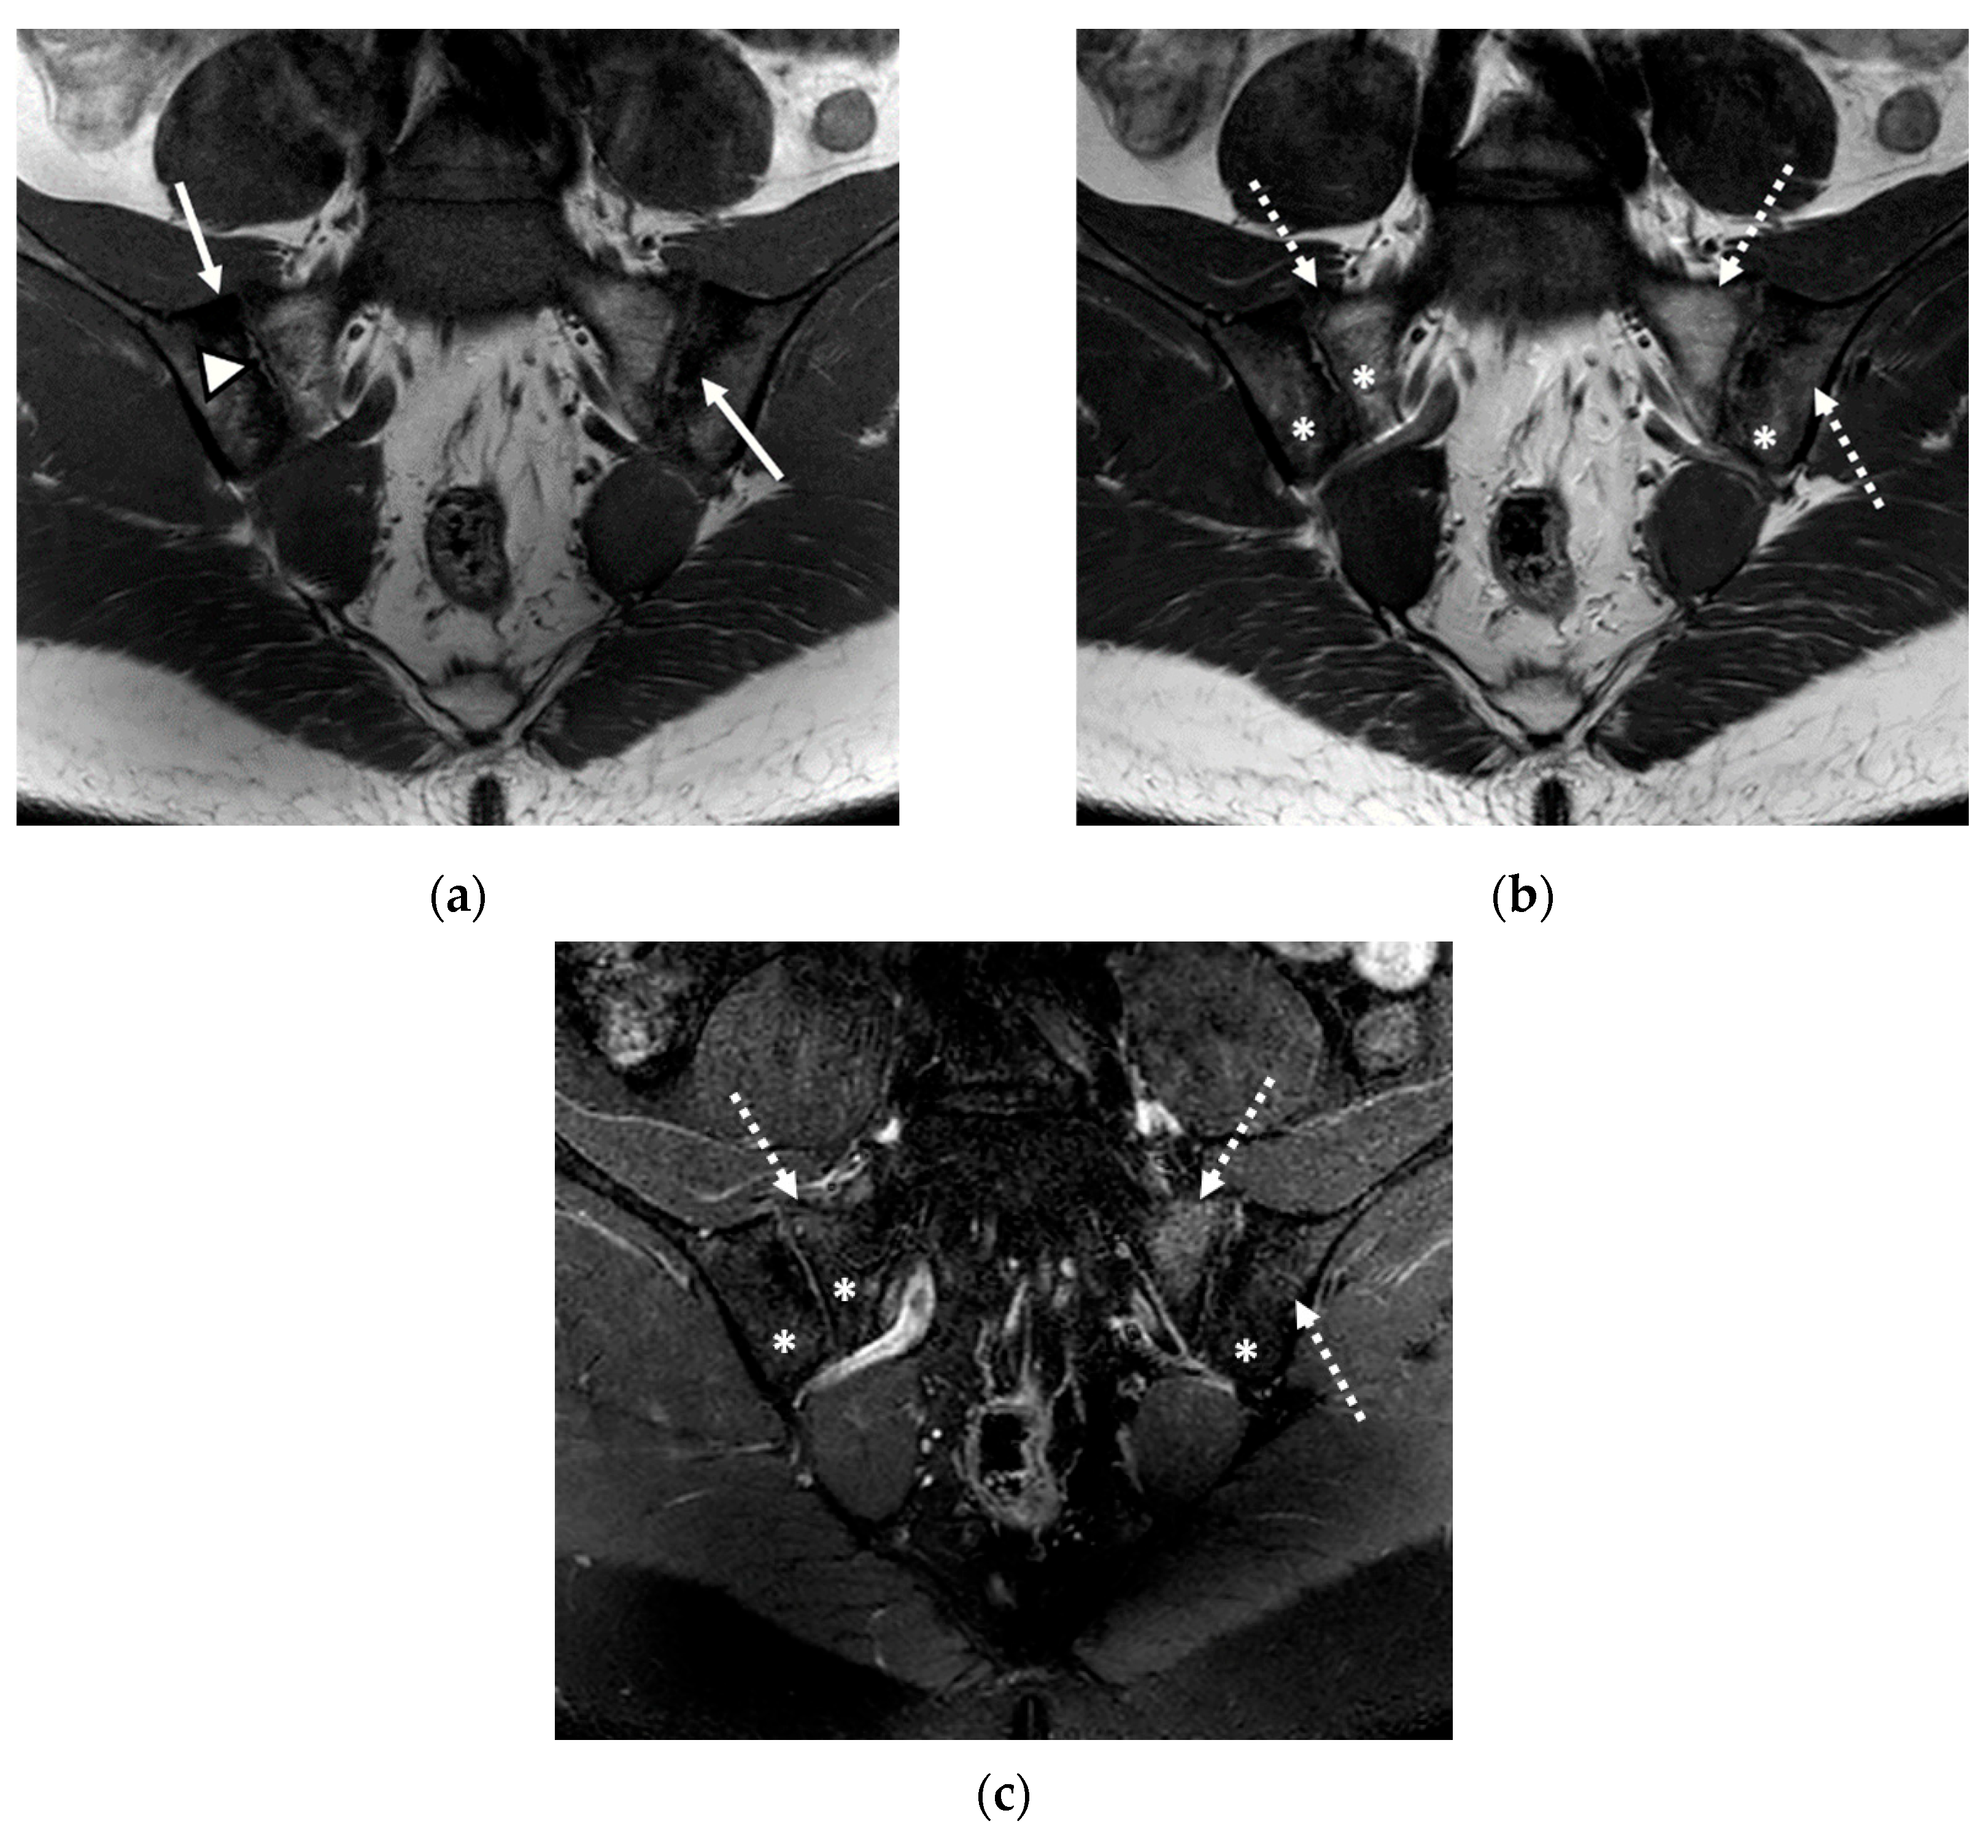

We evaluated 68 sacroiliac joints. The prevalence of MRI-detected abnormalities is presented in Table 2. The results of the SR were considered as the reference data. Inflammatory and structural changes were detected on the MRI sequences of the sacroiliac joints. The most frequently encountered inflammatory change, both on the left and right sacroiliac joint, was the presence of bone marrow edema (44.11–58.82%), followed by enthesitis (17.64–26.47%) and synovitis (11.76–17.64%). Regarding structural changes, the most prominent was subchondral sclerosis (50–59.37%), followed by erosions (35.29–41.17%), joint space narrowing (38.23%), fat metaplasia (17.64–23.25%), and backfill (11.76–20.58%) (Figure 1, Figure 2 and Figure 3).

Figure 1.

The magnetic resonance imaging (MRI) examination of the sacroiliac joints revealed narrowing of the sacroiliac joint spaces with bilateral marginal bone erosions (continuous arrow), bilateral subchondral sclerosis (arrowhead), and increased fat metaplasia (star), with minimal diffuse adjacent bone marrow edema (dotted arrow): (a) T1-weighted sequence; (b) T2-weighted sequence; (c) short tau inversion recovery (STIR) sequence.